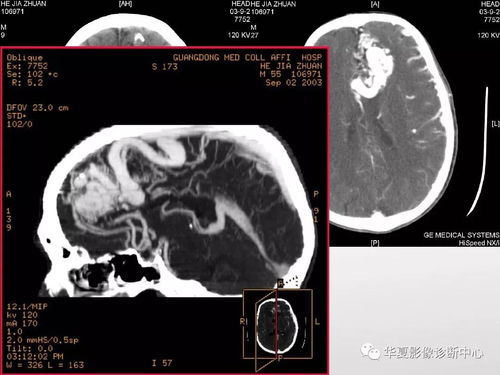

请尽快到心内科就诊,完善心电图、心肌酶、冠脉CTA等检查。健康无小事,及时就医是最安全的选择!